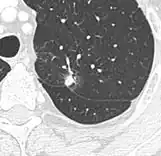

-

subpleural nodule.[9] -

Round well-delineated solid lung nodule with smooth border.[9] -

Lobulated nodule.[9] -

Spiculated lung nodule.[9] -